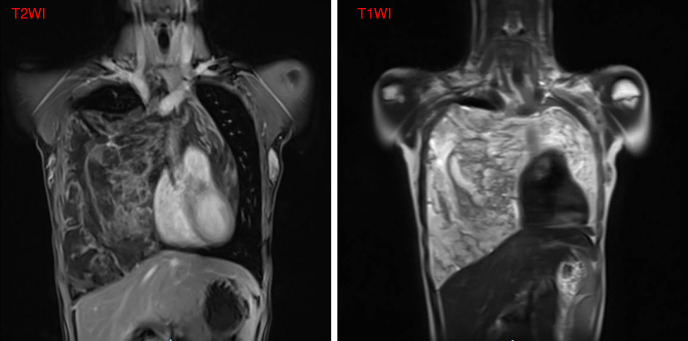

Case description: A teenage girl was diagnosed with a giant thymolipoma, which was discovered incidentally during a routine chest radiograph. Notably, the patient remained asymptomatic despite the tumor's considerable size and its apparent impact on surrounding thoracic structures. To facilitate a thorough preoperative assessment, a multimodal imaging approach was employed, including contrast-enhanced ultrasound (CEUS), computed tomography (CT), and magnetic resonance imaging (MRI). These advanced imaging techniques played a crucial role in delineating the tumor's extent, characteristics, and relationship to adjacent anatomical structures, thereby informing surgical planning. Ultimately, the tumor was successfully excised through a median sternotomy. Postoperative pathological examination confirmed the diagnosis of thymolipoma. Remarkably, after a follow-up period of five years, the patient showed no signs of recurrence and maintained a healthy status.